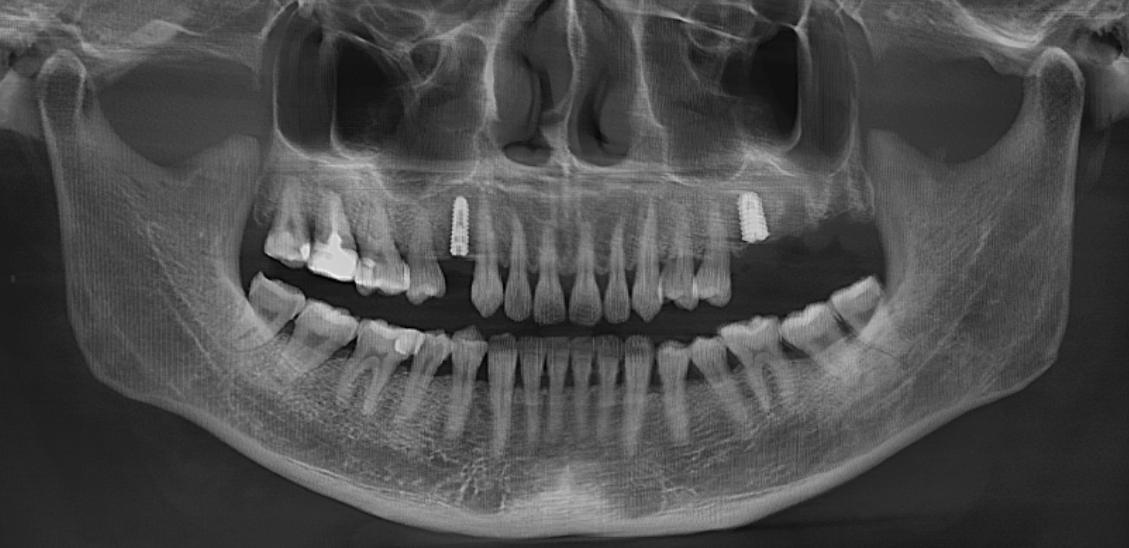

(种植术后全景片)